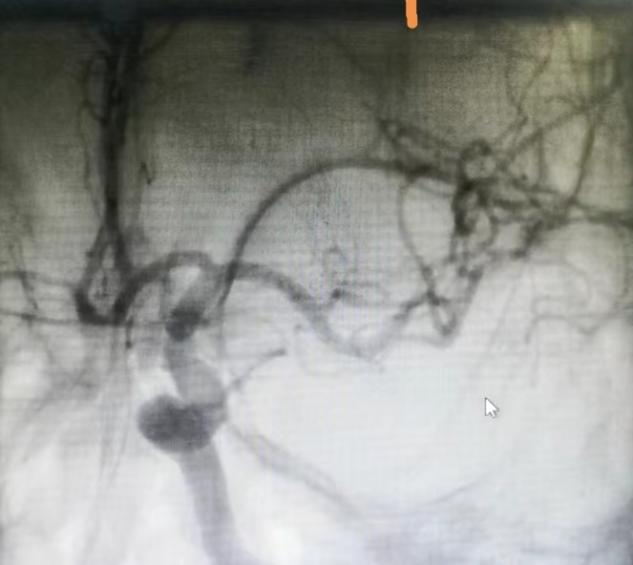

堵塞的左侧大脑中动脉